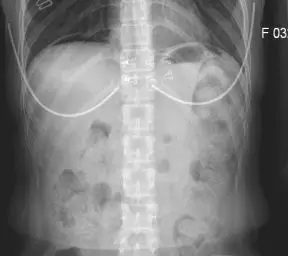

女,33岁,2017年1月9日因反复下腹疼痛2日,再发加重10小时入院,入院查体呈腹膜炎体征,中下腹可扪及约8×12cm大小质硬包块。腹部平片可见膈下游离气体(图1),CT示:乙状结肠肠壁增厚(图2),血常规:白细胞19.6 ×109/L,C反应蛋白54.9mg/L,中粒细胞分类92%,血红蛋白114.0g/L。

图1 膈下游离气体